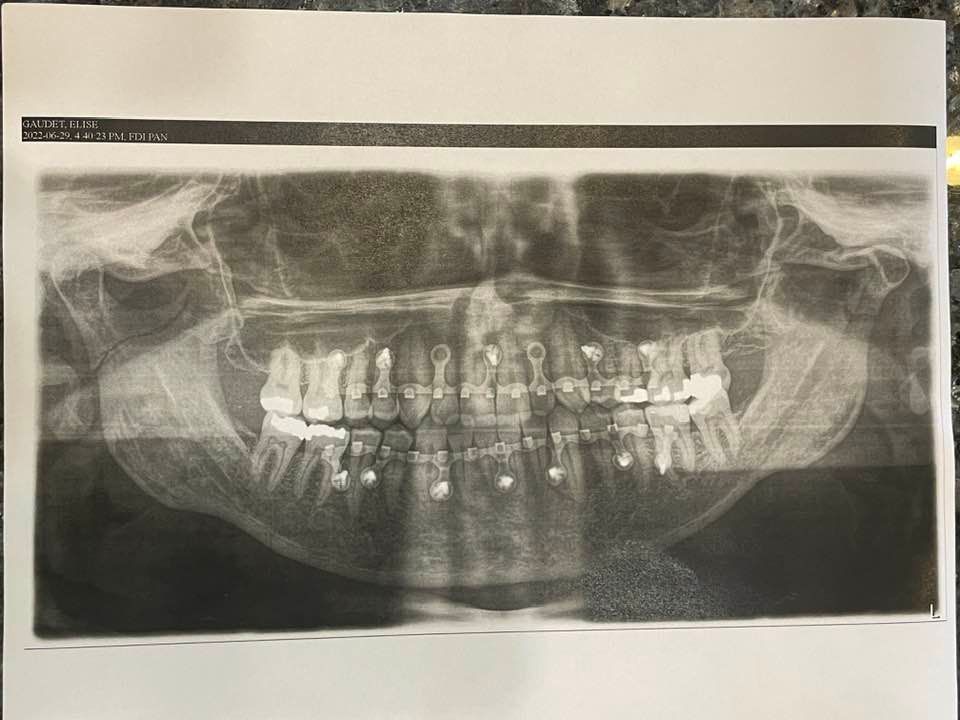

You might only connect with me and our company online but I have a short story to share and I hope we can all take away something from my experience. Normally, I'd share a picture from a ride, showing some beautiful scenery that we came across but this picture represents my summer riding best, unfortunately. It has been a summer like none other for me. As you might know from your own experience or from other cyclists you know, accidents happen. No matter how careful you are, we also rely on other trail and road users to do their part, to follow the law, to be responsible and to pay attention and exercise good judgment. But accidents can still happen. Most often, I've gotten some road rash and a few scratches to my bike but I've always been able to get back up and ride it home. A few times, I've had blood running down my arm or my leg from some of the deeper wounds but I've rarely really been taken out. On June 28th, though, I had a bad one. I'll try to be brief. (I often fail.) I was riding home from work and took the slightly longer route which took me on a multiuse trail. These trails are paved paths that are closed to vehicle traffic and they are wide enough to easily accommodate two-way traffic. In fact, they do have a dividing centre line. Cyclists share these paths with walkers, runners, people walking their dogs, e-scooters and e-bikes. It was around 7PM and a windy, cool night so the trail was quiet. I had the southbound lane to myself and there was a young man walking his dog, a boxer, coming towards me about 300m, on the north bound lane. The guy was not paying attention; he had his phone in his right hand and he was looking at it and only at it. As I got within 100m, the dog is looking at me and starts to look excited. Since the guy walking the boxer still hadn't looked up from his phone, I approached very cautiously, slowed down substantially and had both hands on my brakes. When I got to about 15m away, the boxer started pulling at the leash, as if trying to run to me. I put my brakes full on, as hard as I could and yelled out something (either "oh" or "no" but I don't remember). I tried to stop on time to avoid hitting the dog but, I didn't quite manage it. I hit the dog and then went right over the bars. I landed on my chin, splitting it open, caught my left hand under the shifters, hit my ribs on the handlebars, got an abrasion on my left cheekbone and my upper lip, and a cut on the inside of my upper lip. I lay coughing on the ground and end up spitting out two little pieces of what used to be part of my teeth. Yup, I was a bit of a mess. Long story short, I suffered a broken finger and am still in therapy in order to get full range of motion back but the prognosis for the hand is very positive. I also broke my jaw in three places and had it wired shut for 6 weeks. The healing continues and my bite is now compromised and the long terms treatment plan is still in the works. Right now, I have a lisp I've never had before and it might go away or I might have to learn to form certain letters or sounds differently. Possible fixes are to reshape some of my teeth, get one crown on the tooth that lost the biggest chunk and orthodontic work to fix the bite. It could be a long and expensive journey still. One thing I am so grateful for is that my dentist is also one of my closest friends and I was very lucky to get expert care so quickly. It saved me a trip to an emergency department that evening which was very much appreciated as the health care system here is extremely poorly organized. But that's not the point of my story for you today. (Although if you have a dentist friend, definitely make some time to show them some love!). |